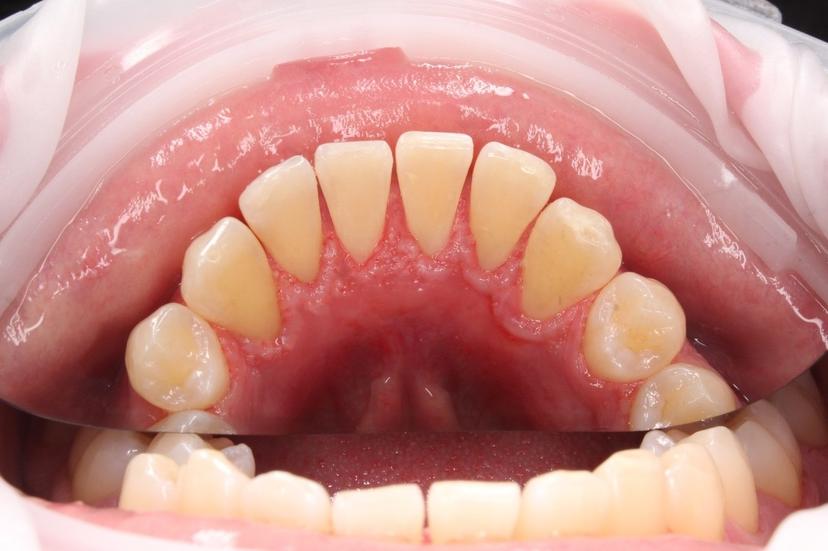

Снятие пигментированного зубного налета системой AirFlow зубов верхней челюсти

Снятие пигментированного зубного налета системой AirFlow на нижней челюсти